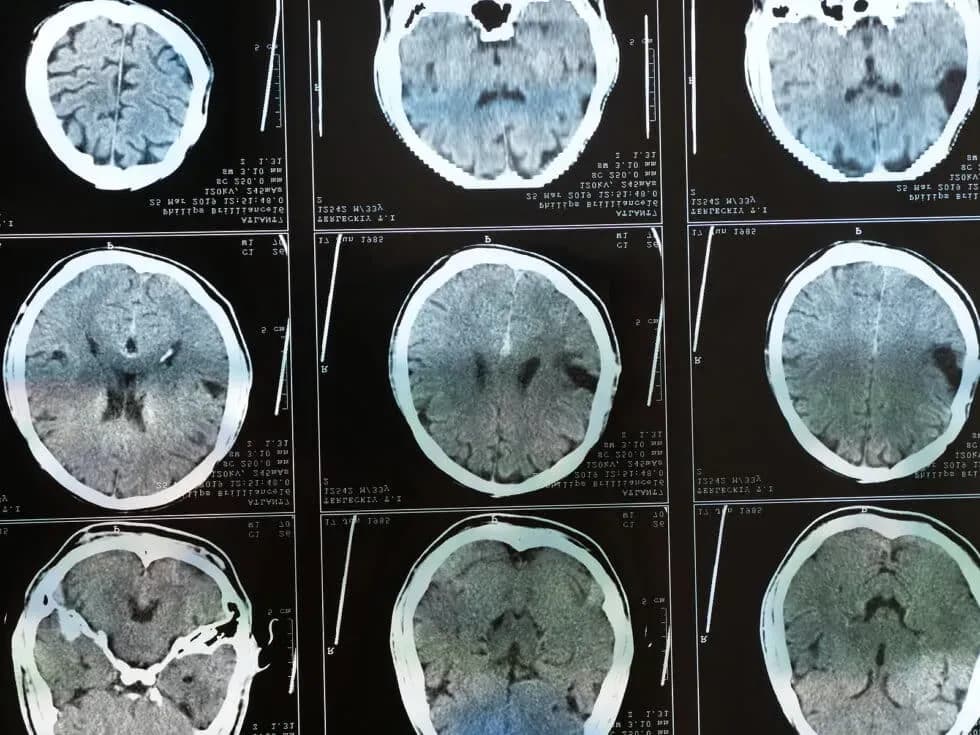

- Examine your medical records, including MRI or X-ray scans